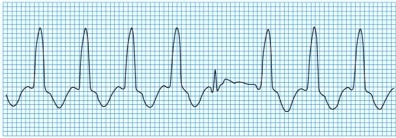

Torsades de Pointes☤

Es debida al QT alargado por la isquemia.

Contribuyen a su aparición los trastornos electrolíticos, y se trata con sulfato de magnesio.